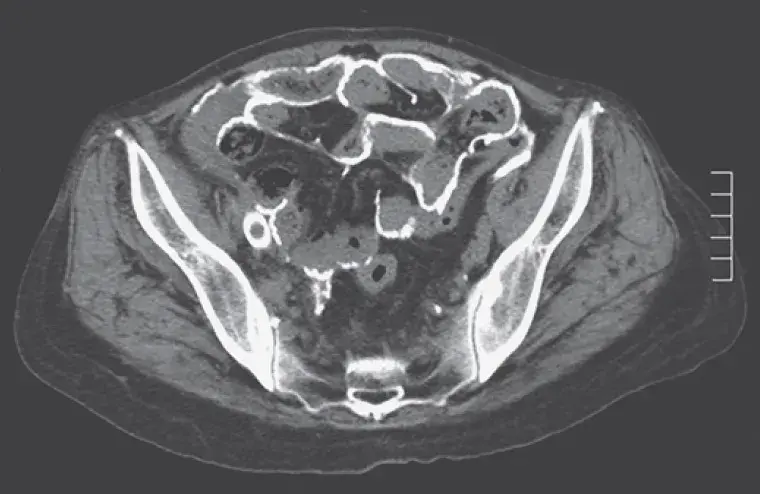

Uma causa incomum de hematúria glomerular intermitente!

Uma causa incomum de hematúria glomerular intermitente!

Hematúria pós infecção, caso clínicos para auxiliar no entendimento de causas glomerulares comuns e raras...